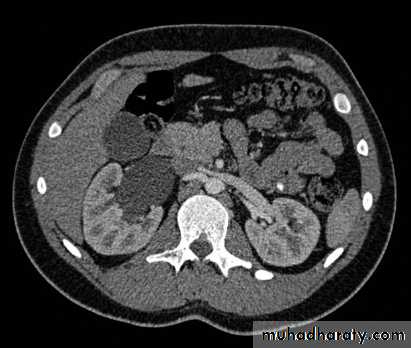

Poly cystic disease

Adult typePresent after the third decade of life , Familial.

Renal parenchyma is replaced by numerous cysts containing fluid , The cysts are of variable size ,

Clinically renal colic, loin mass , heamaturia and hypertension, Renal tissue interposed between the cysts after time dssimcted ended with renal failure

Almost bilateral.

IVU

Large kidney .Lobulated out-line.

Distortion of pelvi- calyceal system depend on cyst size, number and position.

In advanced cases there is elongation and stretching of minor and major calyces ( spider leg).

In advanced cases IVU shows non-functioning kidney .